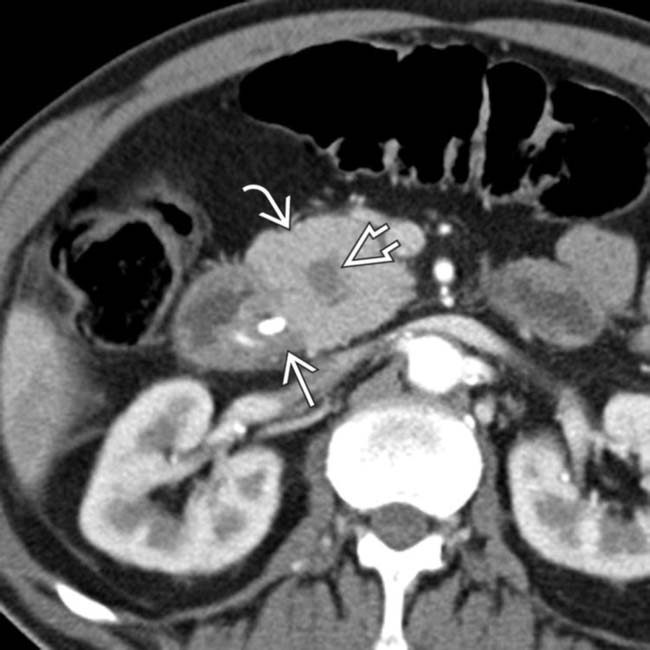

Axial CT image of groove pancreatitis with paraduodenal cysts and Groove Pancreatitis Meaning Groove pancreatitis is a rare form of chronic pancreatitis affecting the “groove” between the pancreatic head, duodenum, and common bile duct. Symptoms present with abdominal pain, obstructive jaundice, and weight loss. Groove pancreatitis (gp) is an uncommon form of chronic pancreatitis (cp). Groove pancreatitis (gp) is an uncommon form of focal pancreatitis characterized by inflammation in the “groove” between the. Groove Pancreatitis Meaning.

A. Axial CT demonstrates the changes of groove pancreatitis with Groove Pancreatitis Meaning Symptoms present with abdominal pain, obstructive jaundice, and weight loss. Groove pancreatitis is a type of chronic pancreatitis that occurs in the 5th to 6th decade of life, with higher prevalence in males than females, and is associated with a significant history of. The exact cause is unknown, although there are. Groove or paraduodenal pancreatitis is an uncommon fibroinflammatory form. Groove Pancreatitis Meaning.